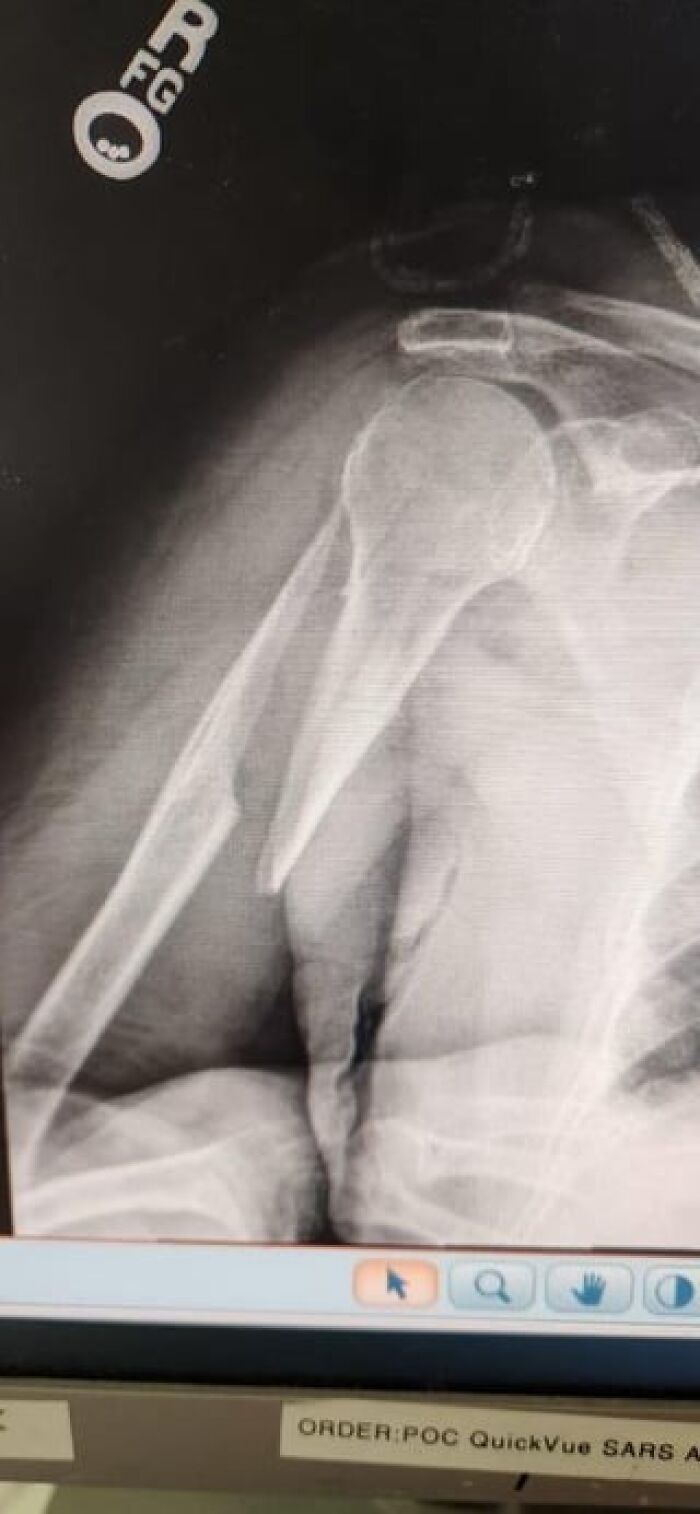

Hospital Staff Freaked Out Over My Bursitis—Thought You Might Be Into It Too